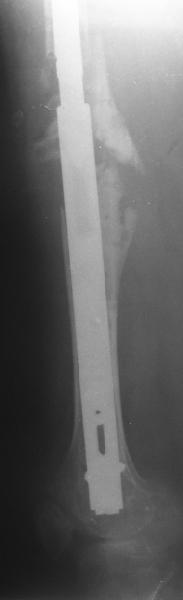

Female, rheumatoid, THA in 2003, car accident in 2006, failed plating. Nailing in Oct 2007. The nail is solid with hollow proximal part where the stem is docked. Last images are in 1 year after

nailing.

The femur responded by failure to Mennen plating (DePuy Bridge plate). So i would add that the ability to unite is realized in mechanically and biologically sound conditions.